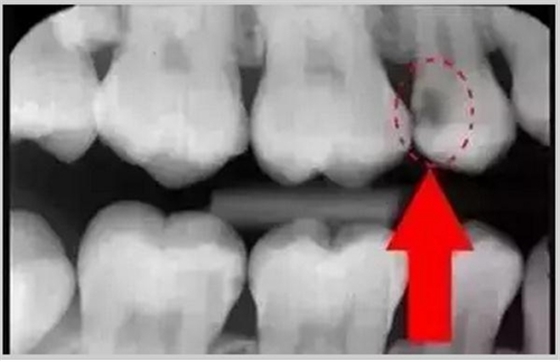

暗的部位說(shuō)明齲齒已經(jīng)非常嚴(yán)重了!

上面這個(gè)是接近牙髓了!